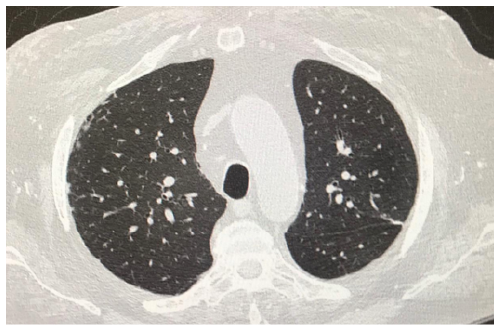

Asymptomatic Testicular Carcinoma Presenting with Metastatic Pulmonary Symptoms: Case Based Review

Cuneyt Tetikkurt, Başak Toksöz and Bilun Gemicioğlu. 12(3): 30-36.